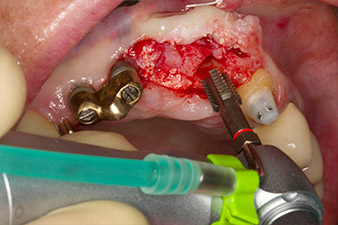

След първичното оздравяване, меките тъкани са оформени посредством базално разположения мост. Два месеца по-късно, обработваното поле е изложено на палатинална алвеоларна инцизия (Фиг 2). Размерите на алвеоларната кост са достатъчни в позиция 22. Фигури 2 и 4 показват препарацията на имплантното ложе, нарязващия винт и имплатирането, използвайки Implantmed.

Новият имплантологичен мотор е използван с подходящите обратни наконечници на W&H.